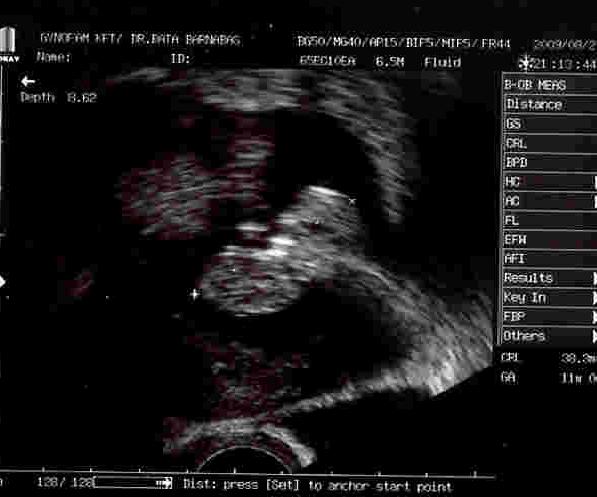

[quote="angie34"]P írta:angie34icibaba vonalzósok: a kalkulátorjuk valamiért egy nappal elszámolja. Ezt már én is tapasztaltam, ezért egy nappl későbbre írtam a szülés várható napját, és így már jól számolja az enyémet (bár az uh szerint 11 voltam tegnap, de én ezután is a menses alapján fogom számolni; még simán behozhatja a lemaradást - ha egyáltalán meg fog születni![]()